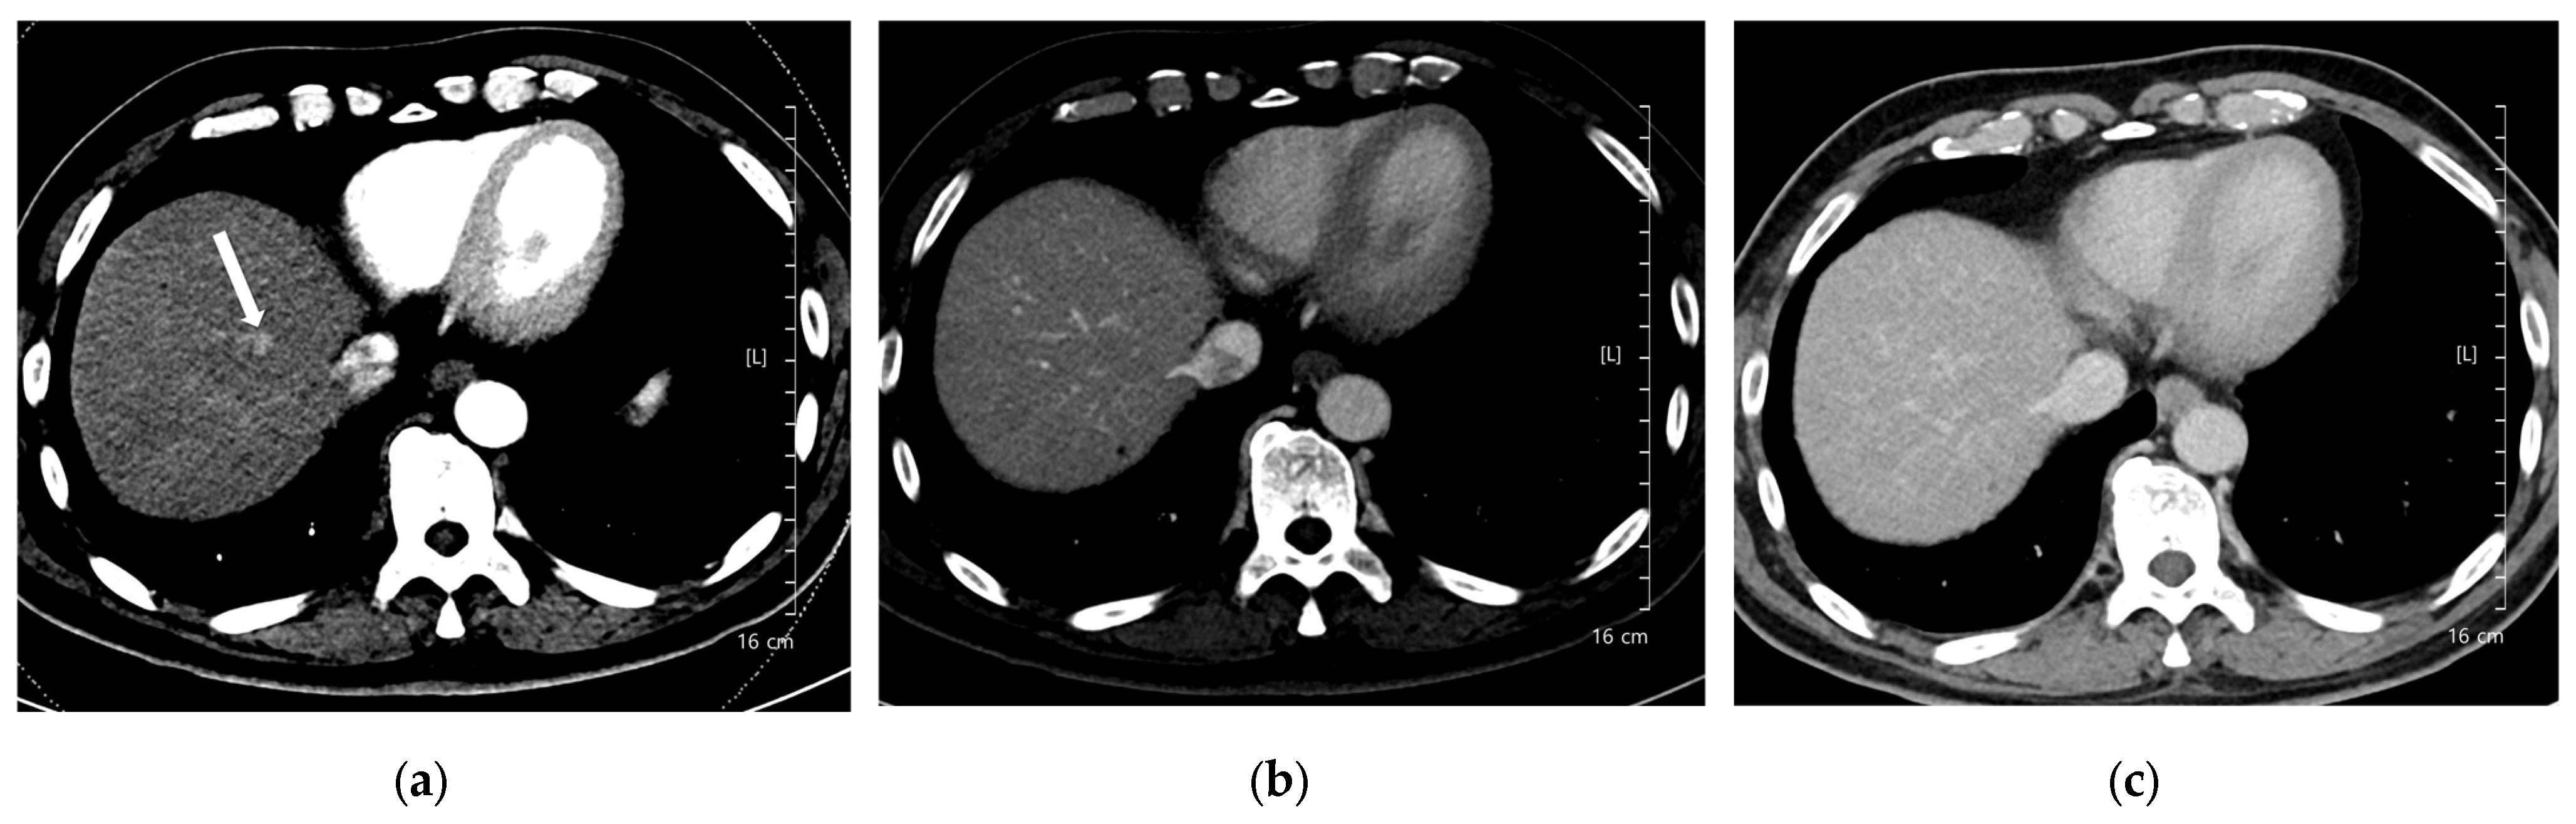

Figure 6. A 91-year-old woman with hepatocellular carcinoma (HCC). CT was performed using low-concentration iodine contrast material (total iodine dose, 518.4 mg I/kg). Overall image quality in the arterial and portal phases was acceptable. (a) An 8-mm enhancing nodule (arrow) is visible on the arterial phase at 100 kVp; (b,c) The nodule shows washout on the portal and delayed phases (arrows). Both reviewers classified the lesion as hepatocellular carcinoma.